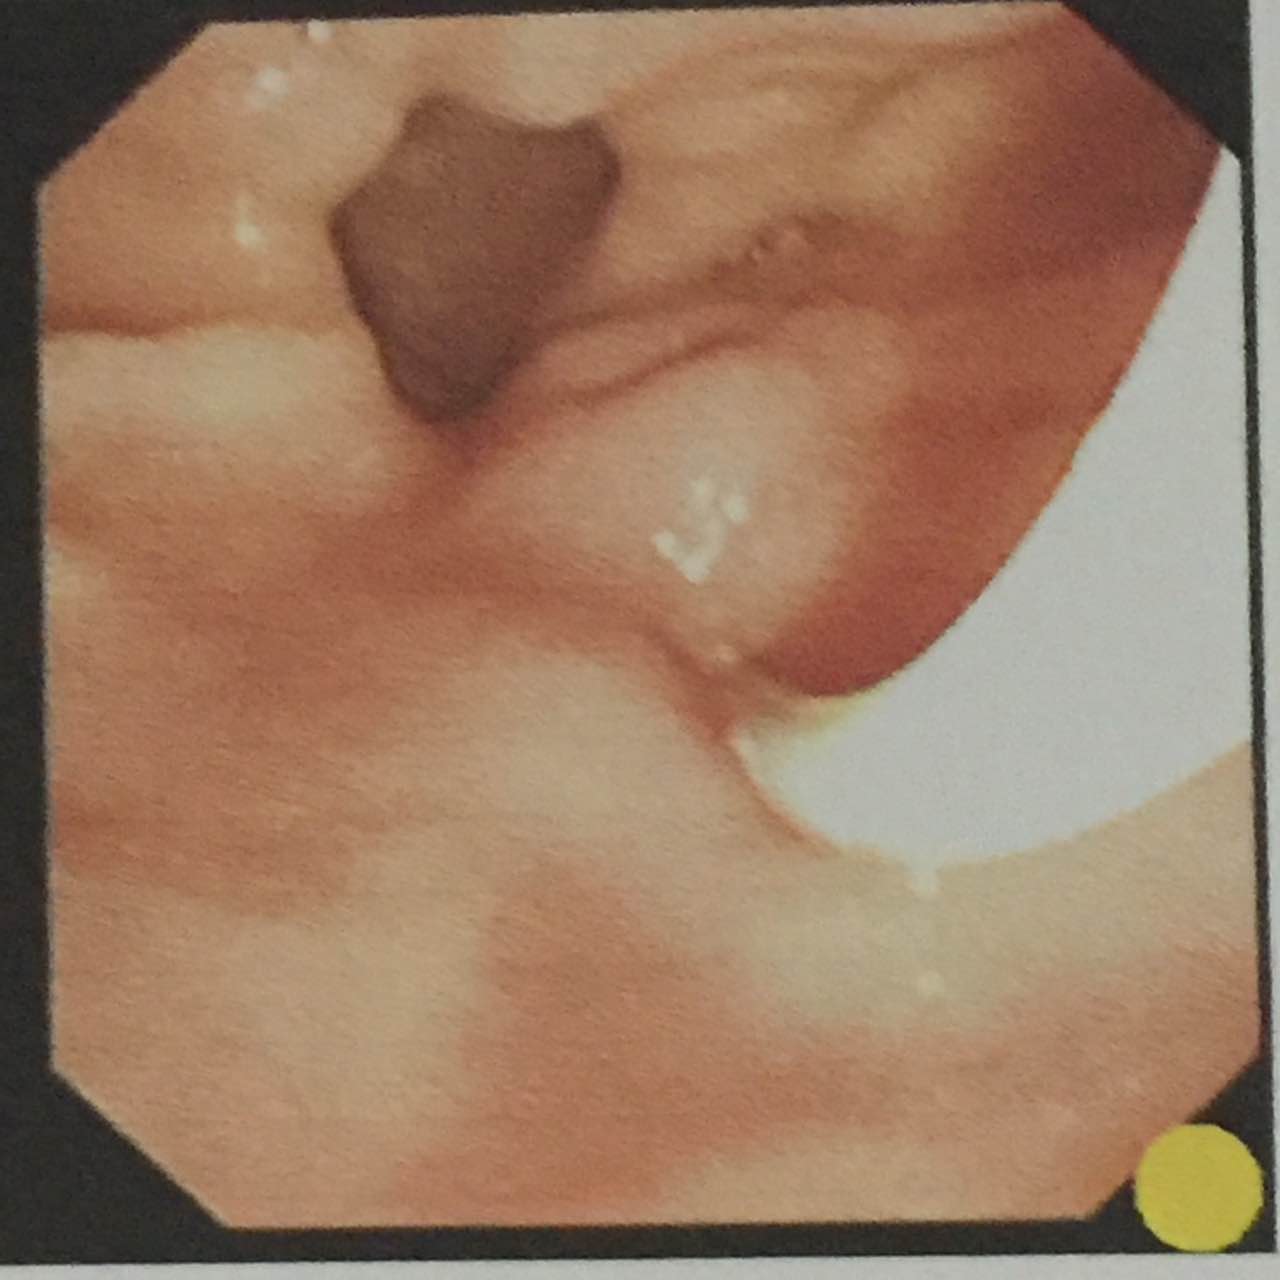

近日,陇南市人民医院消化内科运用ERCP治疗胰胆疾病的微创术成功完成一例十二指肠镜逆行胰胆管造影(ERCP)术+内镜下鼻胆管引流(ENBD)术。该项技术的成功开展,填补了我院在ERCP微创治疗方面的空白。

患者因“上腹疼痛不适1月,加重伴恶心、呕吐1天”入院,入院后行上腹部B超示:胆囊体径增大、腔内结石,肝外胆管扩张。考虑到传统手术治疗胆总管结石对患者伤害较大,为了更加安全高效,陈洮明副院长和主治医师刘健对患者病情进行了详细评估,经过缜密的术前讨论后,建议行ERCP+ENBD术治疗。

4月2日,科室使用医院最新引进的全新高清电子十二指肠镜为患者手术,在陈洮明副院长的指导下,主治医师刘健操作, 护士王秀英、党海珍协作,并在放射科的大力支持下行ERCP+ENBD术,手术过程非常顺利,术后患者未诉特殊不适,术后经常规抑酸、抗感染等治疗后,患者症状明显好转。

经内镜逆行胰胆管造影是将纤维十二指肠镜插至十二指肠降部,找到十二指肠大乳头(下简称乳头),由活检管道内插入塑料导管至乳头开口部,注入造影剂后x线摄片,以显示胰胆管。本法于1968年由mccunne氏首先报导,后由大井等人使本法日趋完善,近十年来,随着器械及插管技术的不断进步,ercp成功率逐年提高,目前已达90%左右,成为诊断胰腺和胆道疾病的重要手段。